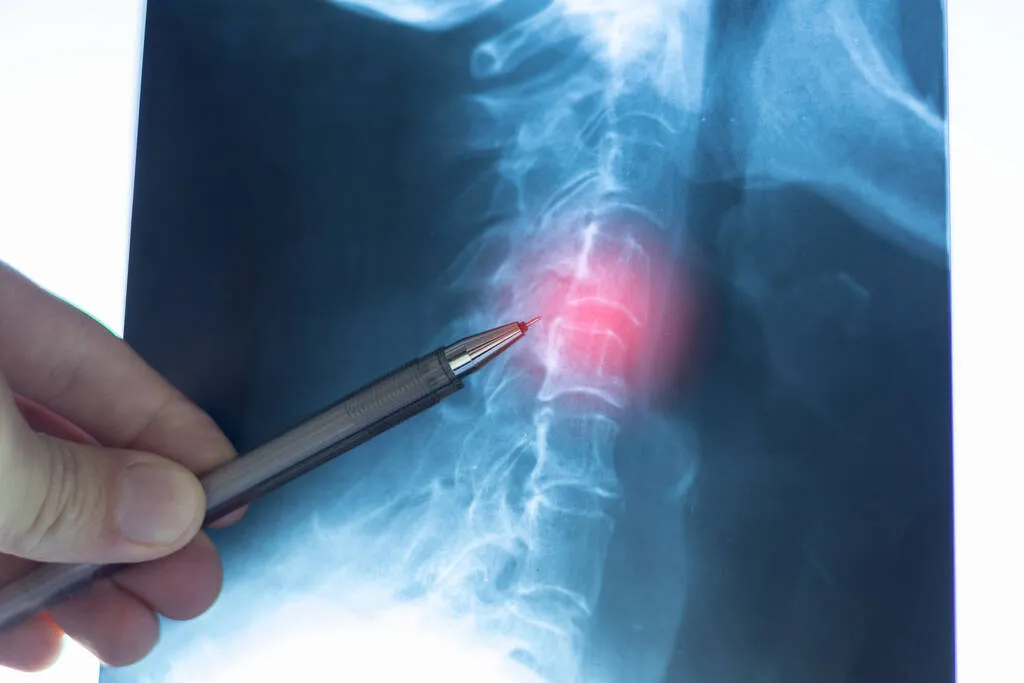

Beyin ve Sinir Cerrahisi Uzmanı Prof. Dr. Selçuk Göçmen, boyun omurgasının başın ağırlığını taşıdığını belirterek baş öne eğildikçe disklere binen yükün arttığını ifade etti. Özellikle sürekli telefona bakan kişilerde risk daha fazla görülüyo.

Dünya genelinde her 1000 kişiden birinin hayatının bir döneminde boyun fıtığı yaşadığı belirtiliyo. Daha çok 40 ile 60 yaş arasında görülse de son yıllarda yaş ortalaması düşmeye başladı.